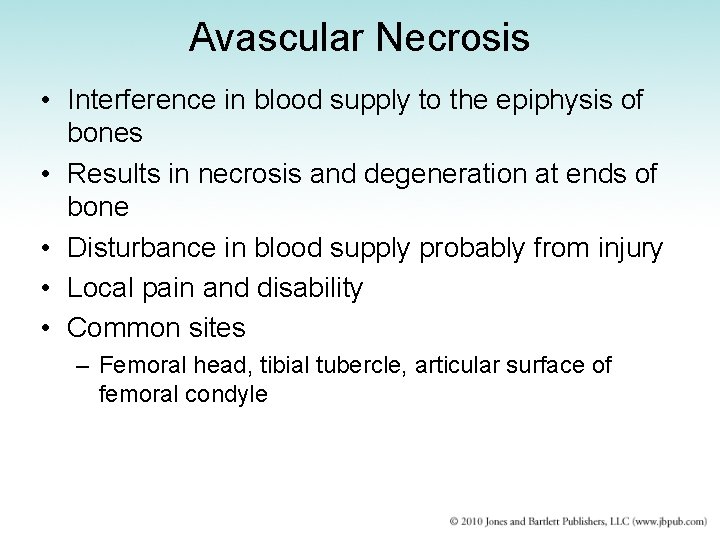

Avascular Necrosis • Interference in blood supply to the epiphysis of bones • Results in necrosis and degeneration at ends of bone • Disturbance in blood supply probably from injury • Local pain and disability • Common sites – Femoral head, tibial tubercle, articular surface of femoral condyle

Avascular Necrosis